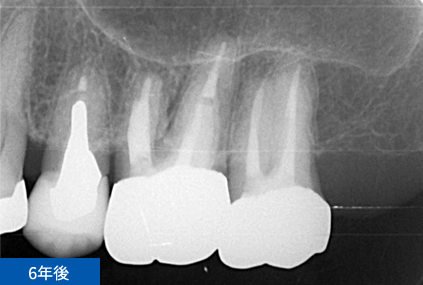

右下6番目の歯が、冷たいものがしみて痛いという主訴でご来院されました。